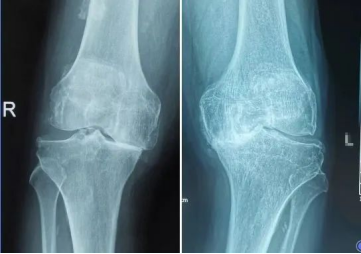

老寒腿其实就是膝关节骨性关节炎,是一种常见的慢性关节疾病,并不是风湿引起。特征是膝关节软骨退行性变,包括关节软骨的磨损和关节软骨的变性退化,以及骨质增生等引起的关节疼痛和关节功能障碍。

关节软骨老化与磨损是老寒腿的真正原因。目前认为增龄、肥胖、外伤、劳损等因素会加快膝关节表面的软骨磨损。